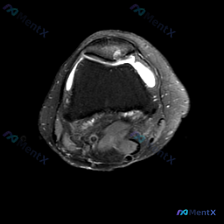

看到这个病例,临床关注点是「膝关节软骨异常」,只拿到了这一张膝关节MRI T1加权轴位图像,整理一下分析思路给大家参考。 一、病例基本影像信息 这是一张股骨远端层面的轴位T1加权图像,先整理一下能看到的信息: 1. 骨结构:股骨内侧髁、外侧髁轮廓清晰,皮质骨连续低信号,骨髓腔内中等信号符合正常表现,...

病例读片:膝关节软骨异常的影像陷阱 先给大家看一下这份病例的基本影像资料:这是一张膝关节MRI-T1加权序列的轴位图像,扫描层面位于股骨远端髁间窝与髌股关节层面。 影像基本信息整理 1. 骨骼结构:股骨远端骨皮质、骨髓信号正常,髌骨形态完整,骨皮质连续,骨髓信号无异常; 2. 关节软骨:髌骨后方关节...

今天分享一个很有代表性的读片病例,核心矛盾是「临床怀疑软骨异常,但单张MRI没看到明确病变」,整理了完整分析思路,大家一起讨论。 病例基础信息 这是一张膝关节MRI的T1加权轴位图像,聚焦显示髌股关节及周围软组织结构,患者主诉提示存在软骨异常相关问题。 影像基础评估结果 1. 骨骼结构:股骨远端滑车...